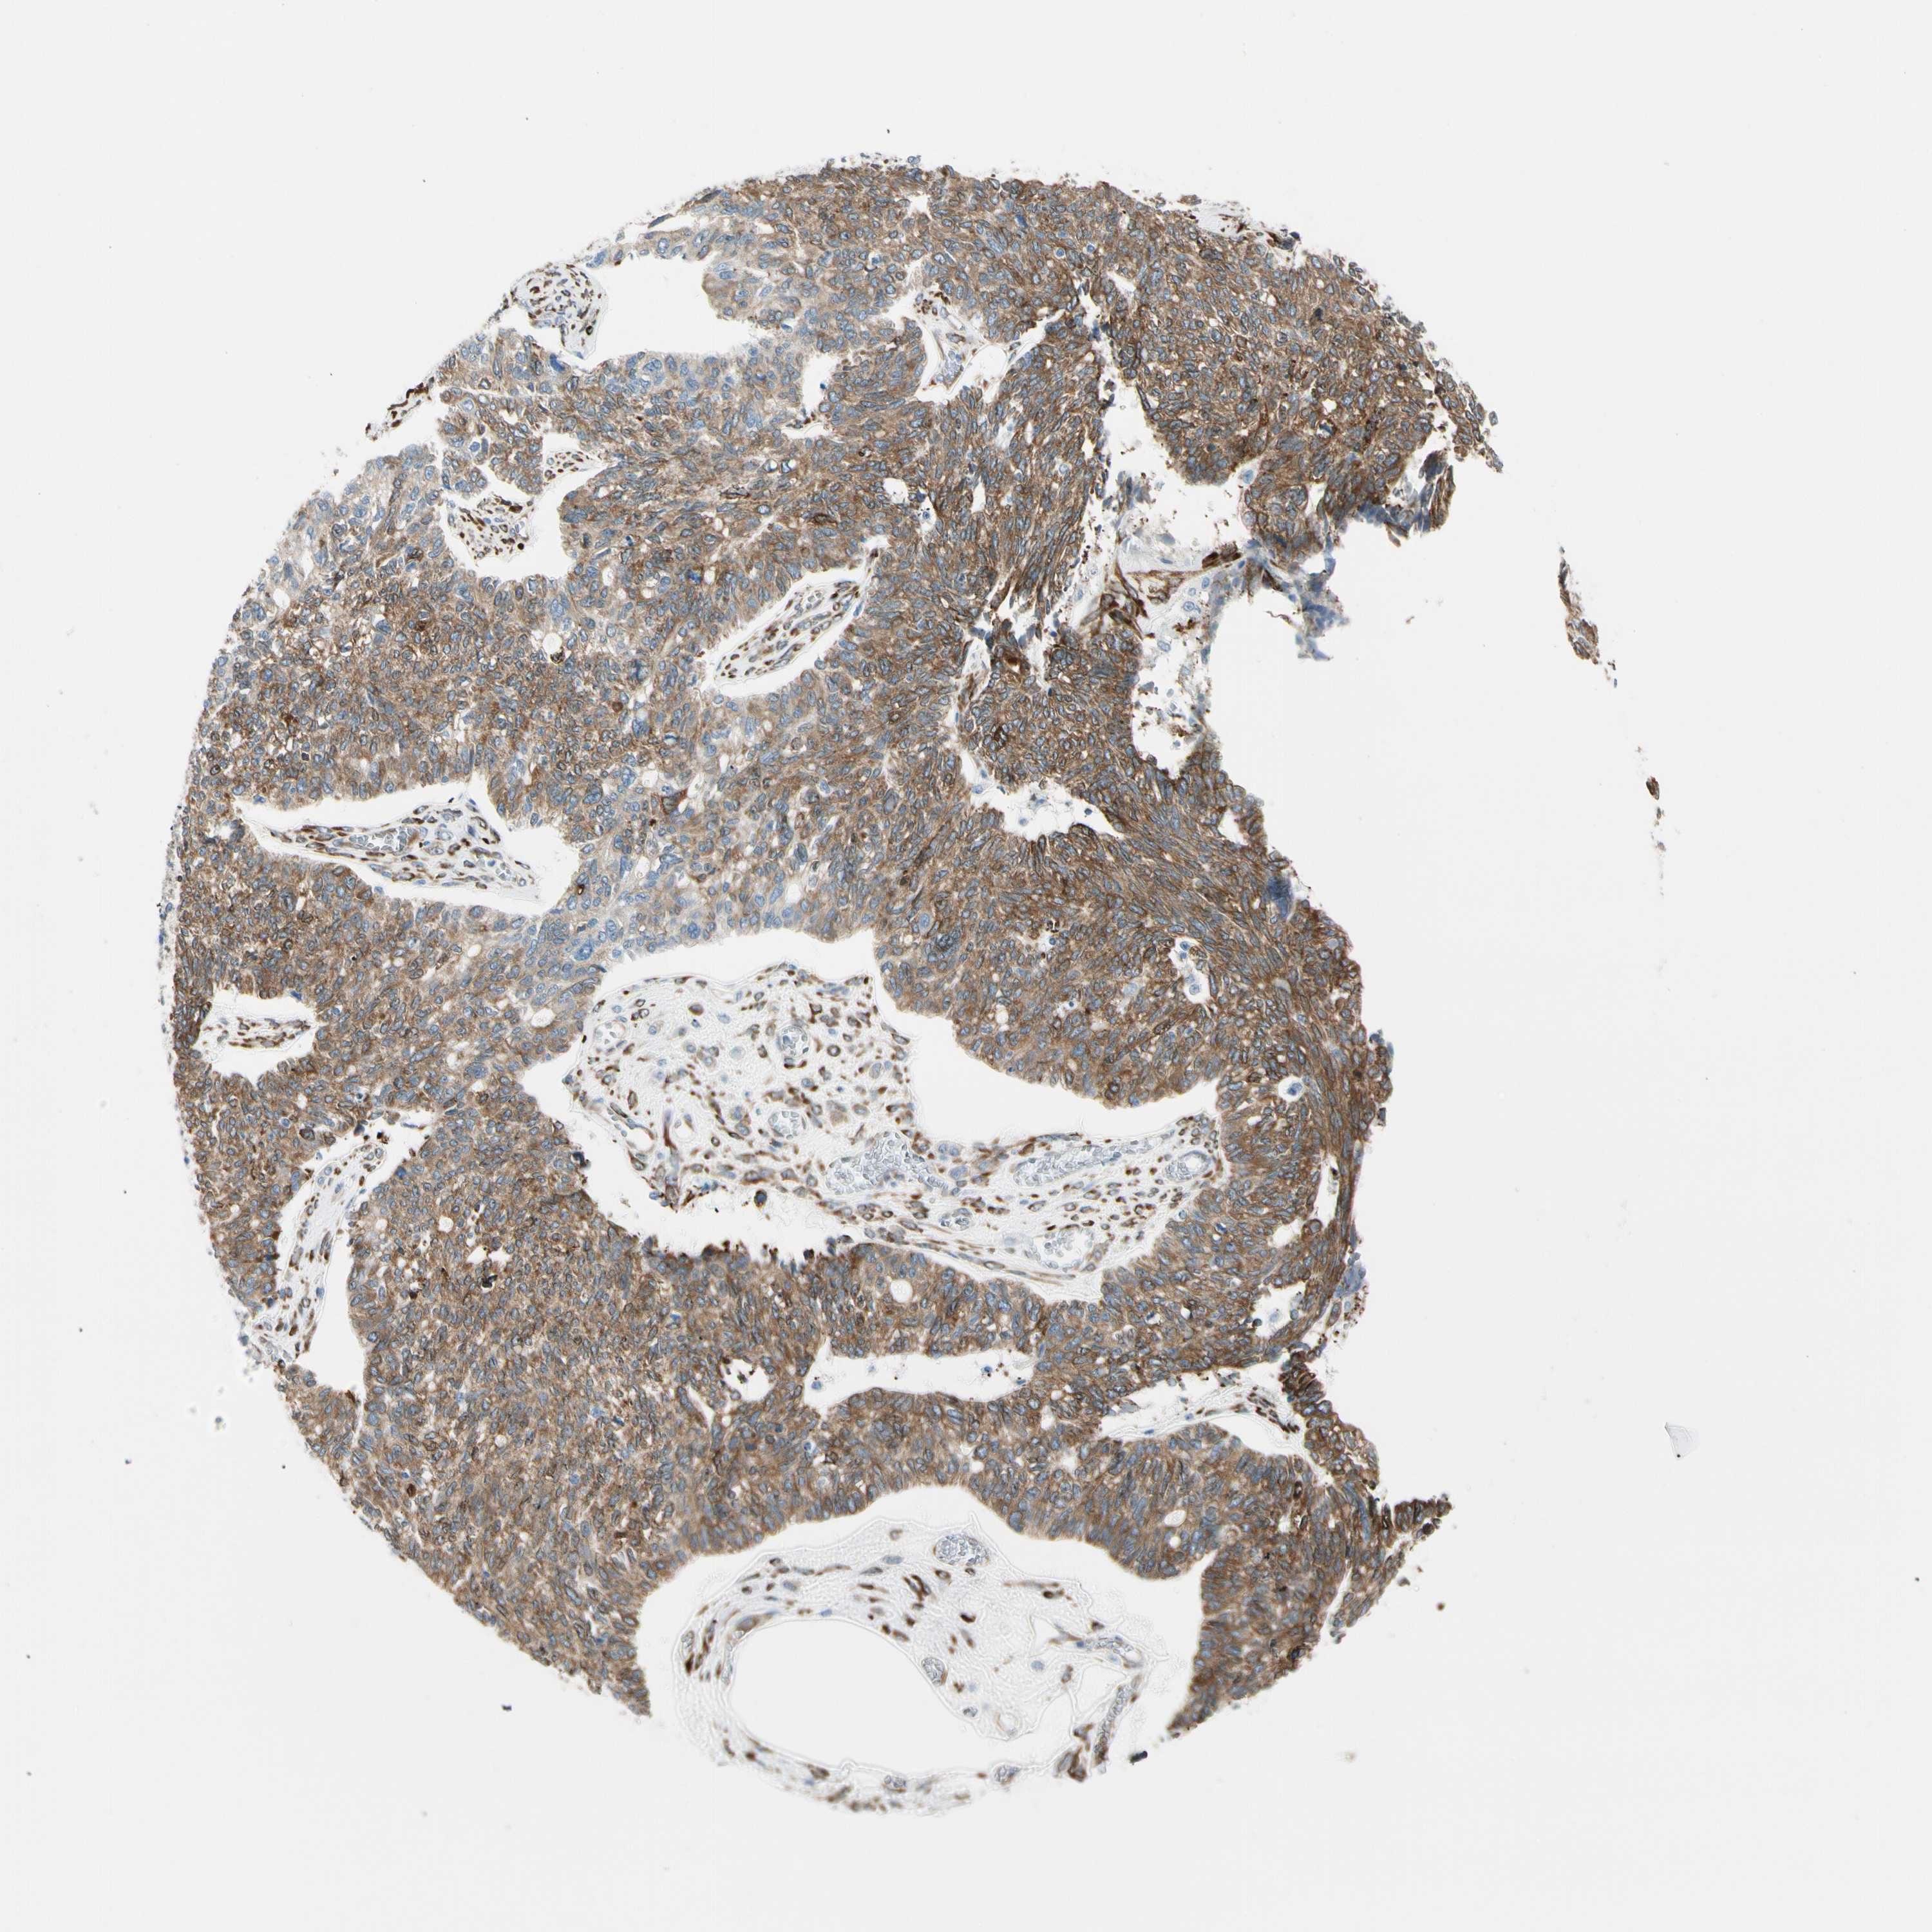

OVARIAN CANCER - Protein expressioni

A mouse-over function shows sample information and annotation data. Click on an image to view it in a full screen mode. Samples can be filtered based on level of antibody staining by selecting one or several of the following categories: high, medium, low and not detected. The assay and annotation is described here.

Note that samples used for immunohistochemistry by the Human Protein Atlas do not correspond to samples in the TCGA dataset.

Antibody stainingi

Antibody staining in the annotated cell types in the current human tissue is reported as not detected, low, medium, or high, based on conventional immunohistochemistry profiling in selected tissues. This score is based on the combination of the staining intensity and fraction of stained cells.

Each image is clickable and will lead to virtual microscopy that enables deeper exploration of all samples and also displays staining intensity scores, fraction scores and subcellular localization as well as patient and tissue information for each sample.

Antibody HPA008707

Staining

High

Medium

Low

Not detected

Intensity

Strong

Moderate

Weak

Negative

Quantity

>75%

75%-25%

<25%

None

Location

Nuclear

Cytoplasmic/membranous

Cytoplasmic/membranous,nuclear

Cystadenocarcinoma, serous, NOS

Carcinoma, endometroid

Cystadenocarcinoma, mucinous, NOS

Carcinoma, NOS